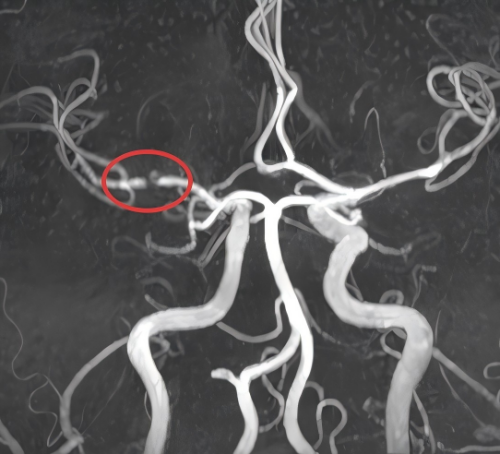

本以为微创术后能安稳下来,然而江女士今年的复查结果,让所有人都捏了一把汗:她的右侧无名动脉血管持续扩张,直径比之前足足增长了1.5厘米以上!在人工血管吻合口的远端,竟然已经同时形成了右侧颈动脉瘤以及右侧锁骨下动脉瘤!这两个动脉瘤随时有破裂风险,一旦破裂就会引发大出血,瞬间致命;若是内部血栓脱落,也会堵塞脑血管,引发脑梗、肢体偏瘫,后果不堪设想。

支架植入后动脉瘤消失